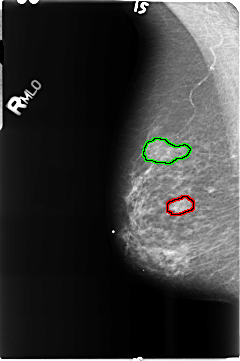

B_3515_1.RIGHT_MLO

FILE: B_3515_1.RIGHT_MLO.OVERLAY

TOTAL_ABNORMALITIES 2

ABNORMALITY 1

LESION_TYPE MASS SHAPE N/A MARGINS N/A

ASSESSMENT 0

SUBTLETY 0

PATHOLOGY BENIGN

TOTAL_OUTLINES 1

BOUNDARY

ABNORMALITY 2

LESION_TYPE CALCIFICATION TYPE PLEOMORPHIC DISTRIBUTION CLUSTERED

ASSESSMENT 4

SUBTLETY 3

PATHOLOGY MALIGNANT